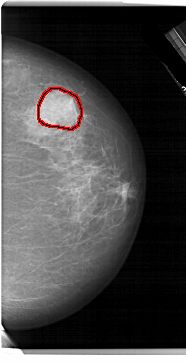

RIGHT_MLO LINES 6496 PIXELS_PER_LINE 3751 BITS_PER_PIXEL 12 RESOLUTION 43.5 OVERLAY

FILE: A_1879_1.RIGHT_MLO.OVERLAY

TOTAL_ABNORMALITIES 1

ABNORMALITY 1

LESION_TYPE MASS SHAPE ROUND MARGINS ILL_DEFINED

ASSESSMENT 4

SUBTLETY 5

PATHOLOGY BENIGN

TOTAL_OUTLINES 1

BOUNDARY